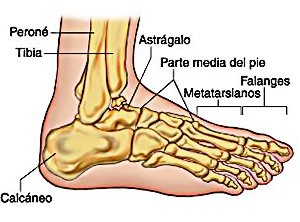

El calcáneo (del latín Os calcis) es un hueso del pie (tarso), corto, asimétrico, de forma cúbica irregular, con seis caras: superior e inferior, laterales y anterior y posterior, de las cuales dos son más o menos articulares.

El calcáneo (del latín Os calcis) es un hueso del pie (tarso), corto, asimétrico, de forma cúbica irregular, con seis caras: superior e inferior, laterales y anterior y posterior, de las cuales dos son más o menos articulares.

Este hueso constituye el talón del pie. Se encuentra en la parte inferior de la primera fila del tarso. Se articula con el astrágalo por arriba y con el cuboides por delante. Constituye el primer punto de apoyo del pie durante la marcha, situándose en una de las zonas peor irrigadas del cuerpo y protegido plantarmente por la almohadilla plantar de tejido adiposo, con función amortiguadora.